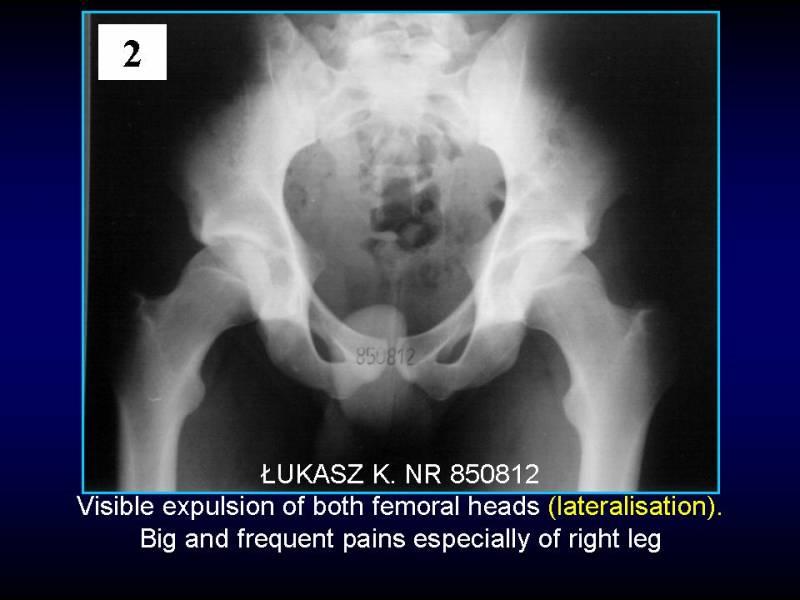

Wody geotermalne w ortopedii. Geothermal water in orthopaedic therapy.